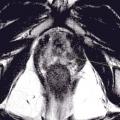

L’IRM multiparamétrique (IRM-mp) de la prostate joue un rôle fondamental dans la détection du cancer de la prostate : le protocole multiparamétrique, qui prévoit des séquences anatomiques en T2, T1 en perfusion (dynamic contrast-enhanced magnetic resonance imaging, DCE-MRI) et en diffusion (diffusion weighted imaging, DWI), est en mesure de fournir une combinaison d’informations anatomiques, biologiques et fonctionnelles nécessaires pour une définition plus précise des lésions suspectes (fig. 1 et 2).

Contrairement à la tomodensitométrie (TDM), la résolution spatiale de l’image garantie par l’IRM permet d’élucider l’anatomie zonale de la glande prostatique et de distinguer la portion périphérique de la glande et le tissu néoplasique, qui a un signal intrinsèque différent. De plus, pour les mêmes raisons, l’IRM est en mesure de mieux représenter toutes les structures pelviennes restantes, avec une clarification remarquable de leurs rapports (vessie, rectum, muscles, structures squelettiques, vaisseaux). Ces caractéristiques rendent désormais l’utilisation de l’IRM multiparamétrique également essentielle à des fins de planification thérapeutique (bilan d’extension locorégional avant traitement local, par exemple de chirurgie ou de radiothérapie externe).